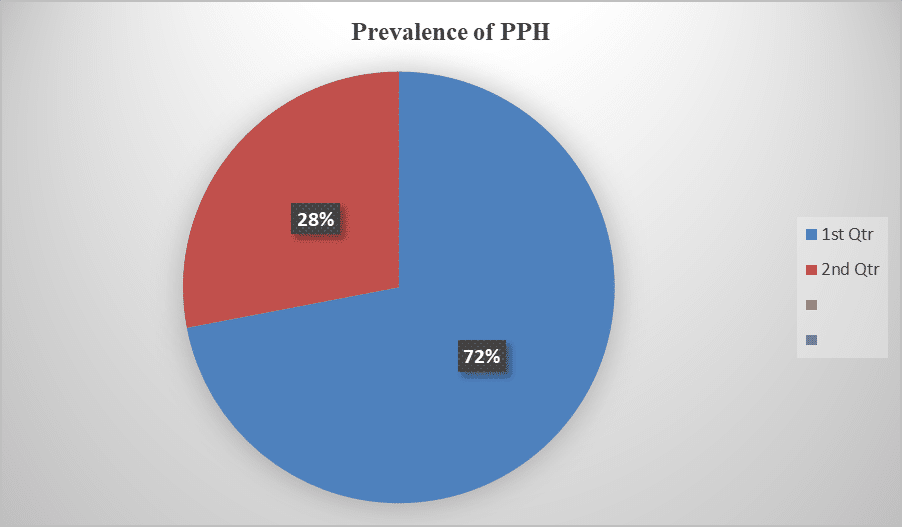

Incidence of Postpartum Hemorrhage in Patients Attending Ongata Rongai Sub-County Hospital in Kajiado County, Kenya

Postpartum hemorrhage is one of the leading causes of maternal deaths during childbirth globally, especially in under developed countries. Kenya’s...Read More